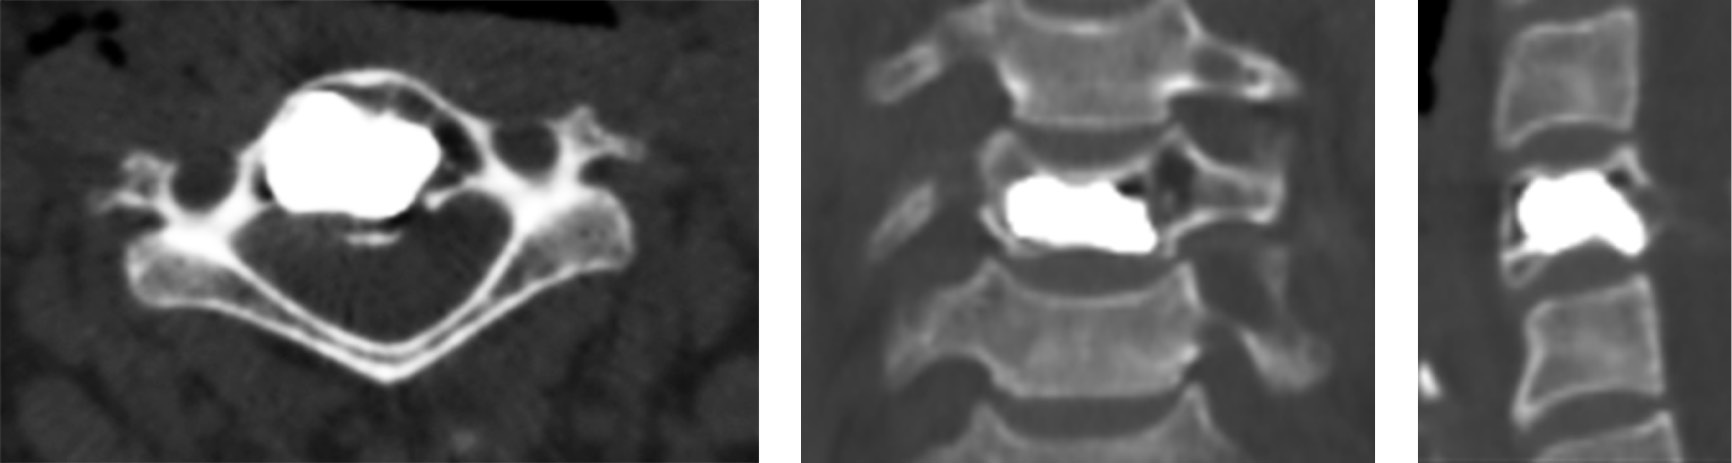

Clinical case 2. Patient V., 17 years old, presented to the institute in May 2018, due to complaints of pain in the cervical and thoracic spine with irradiation to the right upper limb. The pains were dragging and periodic, aggravated by physical exertion. The patient estimated her pain at 6 points as per the VAS. On palpation of the spinous processes of the С7–Th1 vertebrae, an increase in pain syndrome was noted. CT examination showed an aggressive hemangioma of the Th1 vertebral body (Fig. 3). In addition to the clinical symptoms, the aggressiveness of hemangioma was characterized by the CT signs, such as bone expansion with protrusion of the cortical layer; a lesion larger than 2/3 of the vertebral body; damage (thinning) of the cortical layer; and uneven trabecular structure of the hemangioma.

Fig. 3. CT scans of the vertebra Th1 of patient V. before the surgery